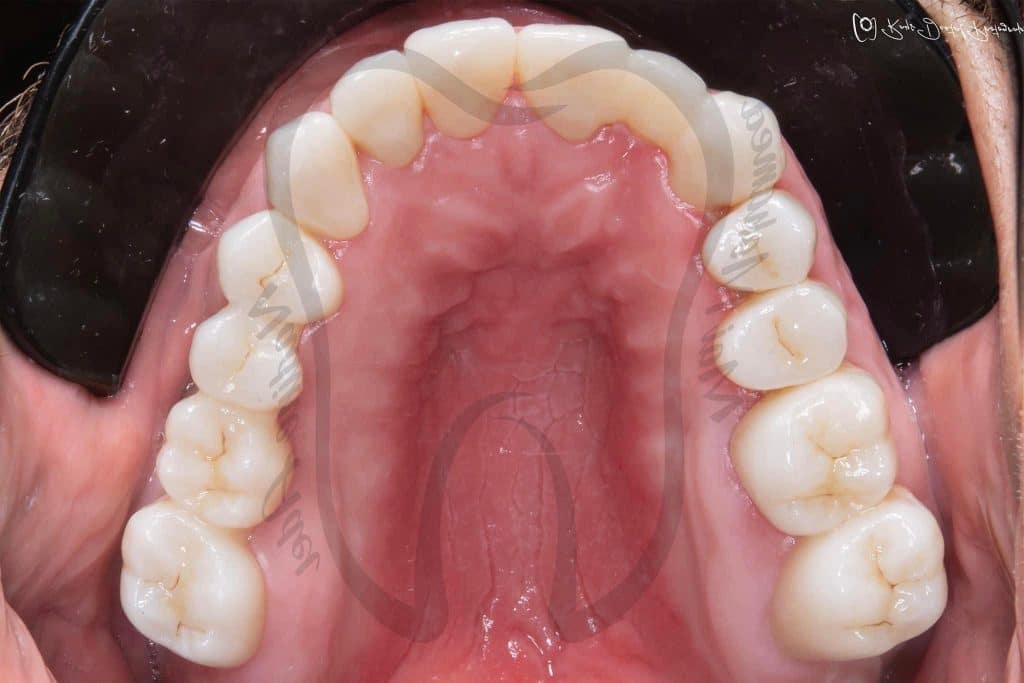

Graduation Case 🎓🎓

5th year student, PUA, Egypt

This case has been done together with my partner Dr Mai Marzouk

Our treatment plan included:

📌 10 Extractions

📌Full Mouth scaling and Root planing

📌 12 Endodontic treatment

📌 6 Post and Core

📌 Full Mouth Composite Restoration

📌 20 Unit Zirconium

📌 5 Unit PFM

📌 Lower Arch Class I Metallic RPD